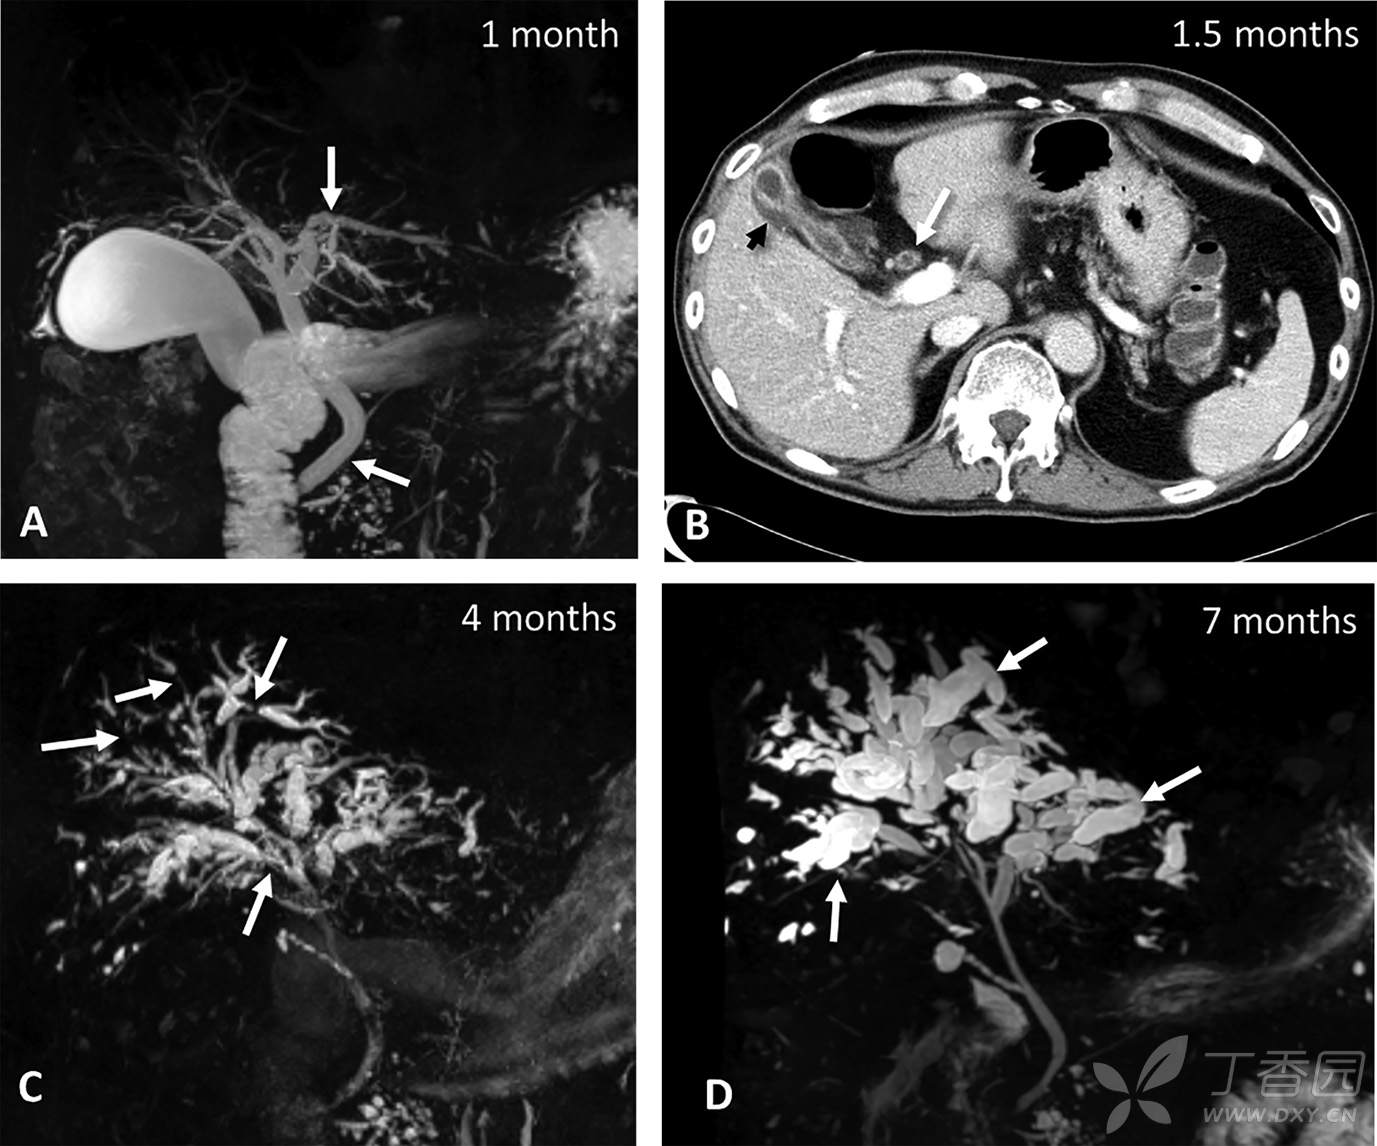

西兰花饺子 推荐一名67岁男性因转移性肺腺癌近3个月来使用帕博利珠单抗治疗。患者出现ALP增高3倍,ALT增高4倍,DBIL增高3.3倍,血清IgG正常。MRCP所见如图A。

随后的ERCP证实胆总管内胆泥及微小结石,予EST后胆道清理。但患者上述生化指标仍持续升高,使后续化疗不能进行。复查CT所见如图B。

行胆囊切除后,患者生化指标仍持续异常,3个月后复查MRCP如图C。遂使用大剂量泼尼松治疗3个月仍无改善,再次复查MRCP如图D。